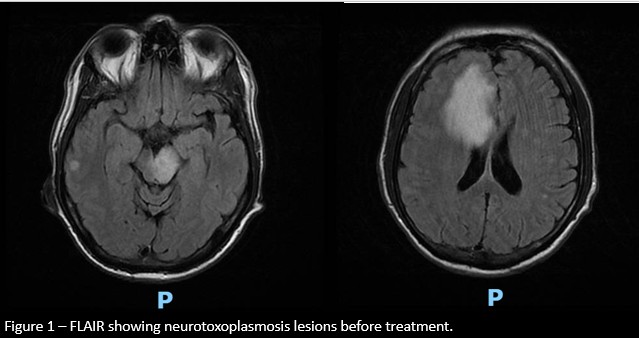

Results: A 58-year-old male patient was admitted for evaluation of one month of anterograde amnesia, accompanied by behavioral changes and hypersexuality. Serological testing revealed HIV positivity, with a viral load of 564,000 copies/mL and a CD4 lymphocyte count of 21 cells/µL. The patient also presented with dysphagia and hiccups, and was diagnosed with esophageal candidiasis. A cranial MRI demonstrated multiple bilateral expansive cortical, nucleocapsular, and brainstem lesions, consistent with neurotoxoplasmosis. Several months later, the patient developed stereotyped, involuntary movements in the right lower limb, present at rest, responsive to sensory tricks, and variable with position, suggesting a dystonic component. A subsequent MRI revealed areas of hemosiderin deposits affecting the left substantia nigra, correlating with the dystonia. A therapeutic trial with levodopa and biperiden resulted in a favorable clinical response.

Figure 1